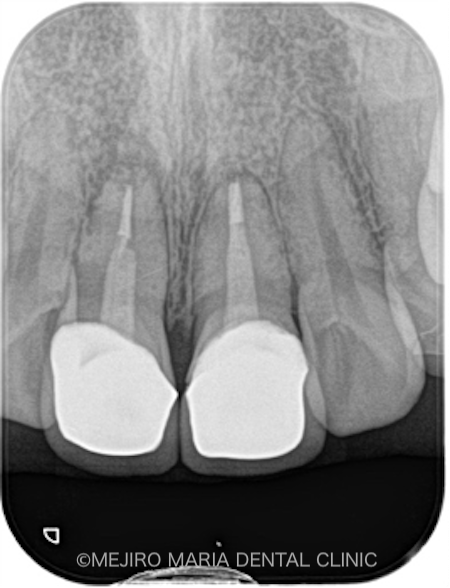

初診時にCT撮影を行い診査したところ、右上1番の根尖の骨は、根尖性歯周炎により喪失していました。また、左上1番の歯にも小さい病変(根尖性歯周炎)が確認されました(2枚目の写真)。